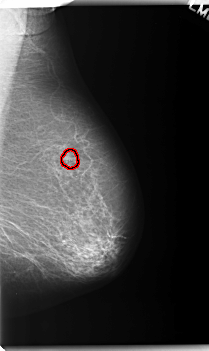

C_0231_1.RIGHT_CC

FILE: C_0231_1.RIGHT_CC.OVERLAY

TOTAL_ABNORMALITIES 1

ABNORMALITY 1

LESION_TYPE MASS SHAPE OVAL MARGINS ILL_DEFINED

ASSESSMENT 5

SUBTLETY 5

PATHOLOGY MALIGNANT

TOTAL_OUTLINES 1

BOUNDARY